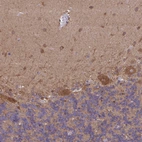

Immunohistochemical staining of human cerebellum shows strong cytoplasmic positivity in Purkinje cells and cells in molecular layer.